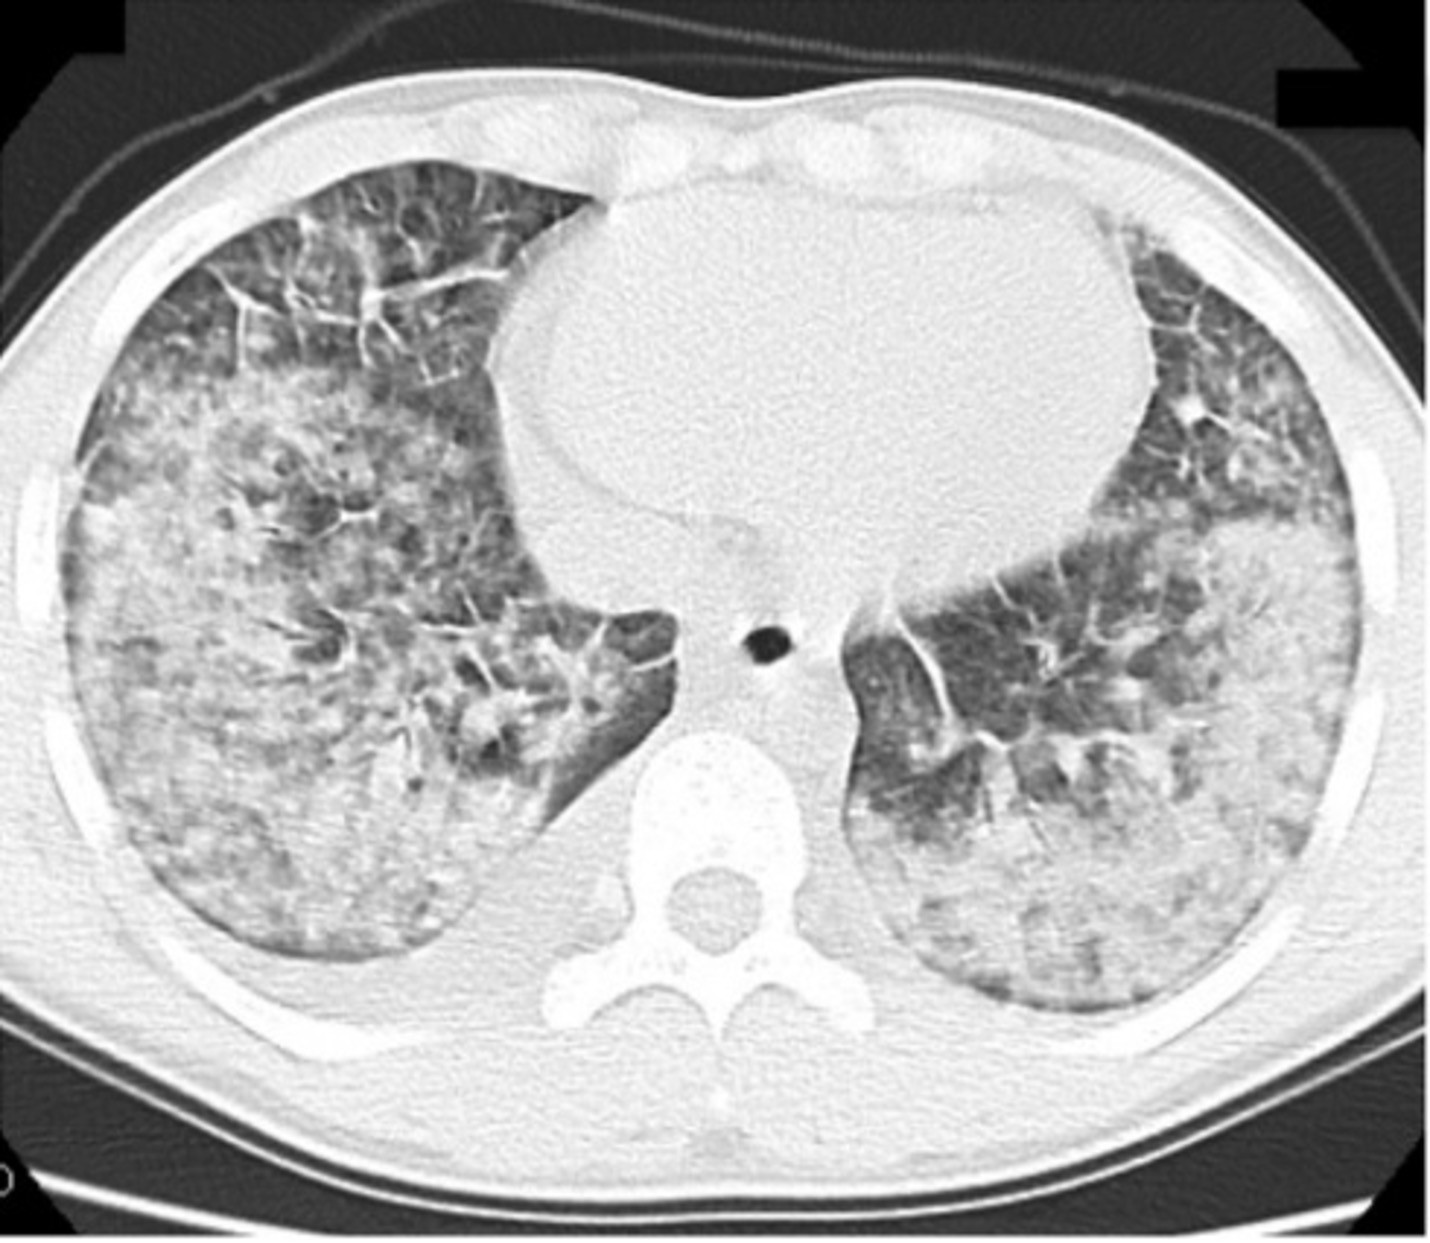

Thứ nhất, thuốc lá điện tử gây tổn thương nhu mô phổi. Hình ảnh kính mờ lan tỏa nền phổi 2 bên, là biểu hiện kinh điển trong bệnh lý này. Các tác nhân có trong thuốc lá điện tử tác động trực tiếp lên phổi, gây ra tổn thương phổi cấp tính đã được ghi nhận là hình ảnh phổ biến nhất trong mô bệnh học.

Đặc biệt, thuốc lá điện tử còn là liên quan một đợt bùng phát bệnh lý mới ở Mỹ khiến nhiều người bị tổn thương phổi. Căn bệnh này được gọi là EVALI (tổn thương phổi cấp liên quan thuốc lá điện tử). Dịch bùng phát mạnh vào tháng 8/2019 và đạt đỉnh vào tháng 9/2019. Tới 18/2/2020, 2807 ca mắc căn bệnh này trên toàn nước Mỹ, 68 ca tử vong được khẳng định có liên quan.

Xét nghiệm dung dịch hút và dịch đường hô hấp các bệnh nhân, các bác sĩ phát hiện vitamin E acetate. Chất này nung nóng trong thuốc lá điện tử tạo thành khí ketene độc. Khi thử nghiệm trên động vật, các nhà khoa học phát hiện chúng gây tổn thương giống ở người.